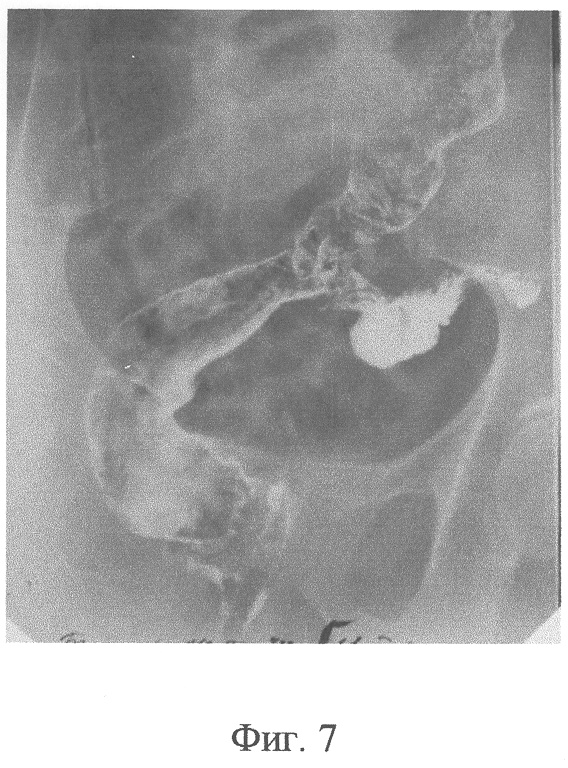

Фиг.7 – контрольная ирригограмма больная Б., 12 сутки после операции: Т-образный толстокишечный анастомоз на этапе функционирующей колостомы;

На 10 сутки после операции компрессионные устройства из зоны образованного анастомоза самостоятельно отторглись и эвакуировались естественным путем, в результате чего сформировалось полноценное соустье (Фиг.6). Колостому на передней брюшной стенке через 16 суток закрыли внебрюшинным способом. После этого, на 9 сутки, больная выписана с хорошей функцией анастомоза (Фиг.7, 8).